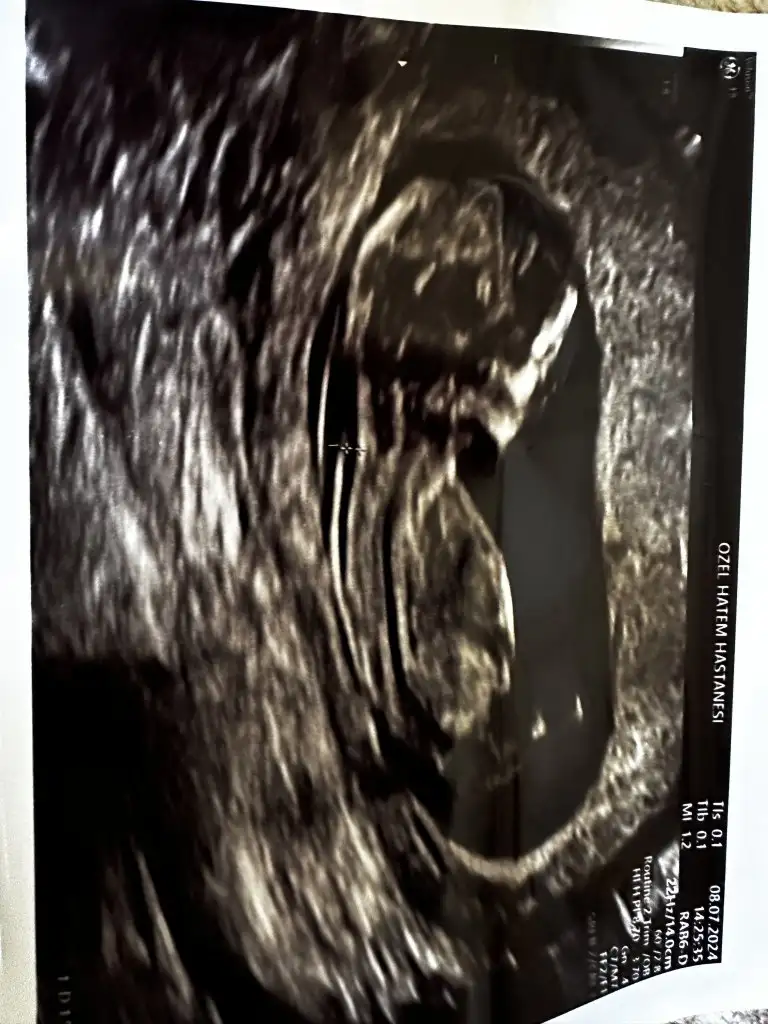

Canım sana yeni resimle geldimSen iste ben sana adli sicil kaydı yoktur belgesi bile atarım

Erkek demiştim dimi kız sana hatırlamıyorum koç gibi yatıyo işteCanım sana yeni resimle geldim